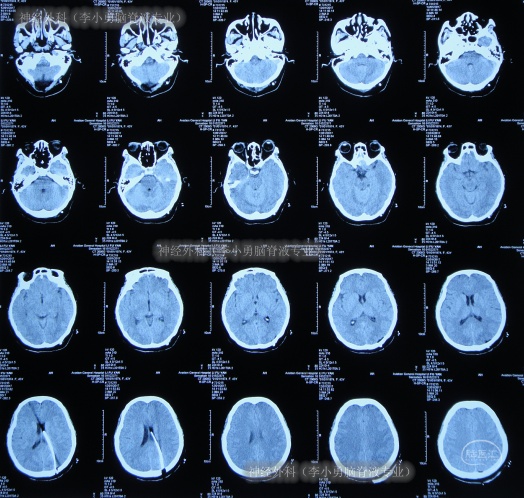

出院后3月半即2017年6月22日,来院复查,复查时:折磨患者间断10年余的头痛终于完全消失了,身体恢复至发病前健康的状态;查头颅CT示无异常(图-16)。

图-16:2017年6月22日

出院后2年零7月即2019年10月23日,来院复查,复查时:身体健康,每天开开心心,查头颅CT示无异常(图-17)。

图-17:2019年10月22日